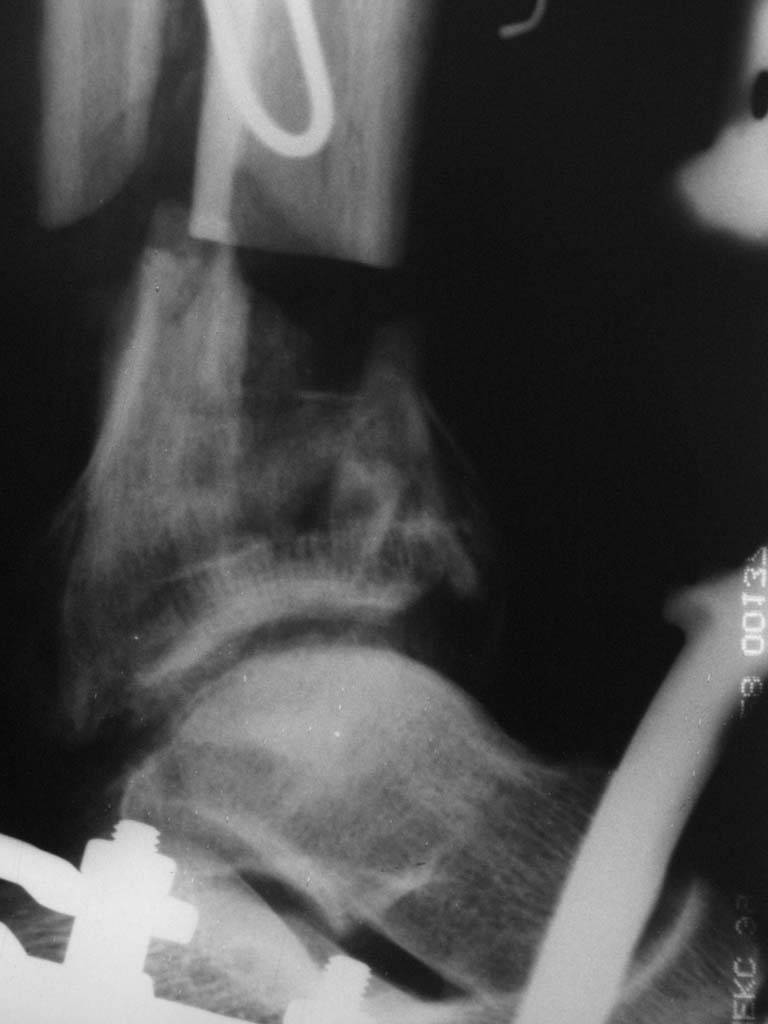

AO Principles of Fracture Management (2000 г.). Прочитав эти доступные книги (ссылки на них выкладывали на форуме не раз) и сделав пару лоскутов в морге можно смело делать эту операцию у живого пациента. Кстати у нас на следующей неделе планируется подобная операция для закрытия раны на пятке. Пусть доктора приезжают, поделимся своим скромным опытом. (рис. 1 , 2, 3 [извините, не успели отмыть кожу от иода], 4)

Больному выполнена резекция малоберцовой кости, ВХО раны, сближение отломков. Резекция м\б через отдельный разрез. После ВХО компрессия в аппарате, края раны сближены наводящими швами (без натяжения).

В случае гладкого заживления раны, при условии положительного решения вопроса с металлом, планируем перемонтаж аппарата Илизарова, дополнительную резекцию дистального отломка, выведение полокости голеностопного сустава в правильное положение (см. боковую Р-грамму), одномоментно остеотомия большеберцовой кости. После восстановления длинны голени, по всей видимости, артродез голеностопного сустава.

Рентгенограммы прилагаются. Фото местного статуса выложу в ближайшее время.

Мы обычно не фиксируем малоберцовую кость. Просто стараемся сопоставить ее концы за счет хорошей репозиции. В представленном случае имеется некоторое смещение дистальных фрагментов кнаружи, и, как мне кажется, ротация их вместе со стопой кнутри (ротация хорошо заметна на прямом снимке по форме таранной кости и на боковом по соотношению отломков малоберцовой). Если это действительно так, то это несложно сейчас постепенно устранить в аппарате. И тогда концы малоберцовой кости будут находиться поближе друг к другу.